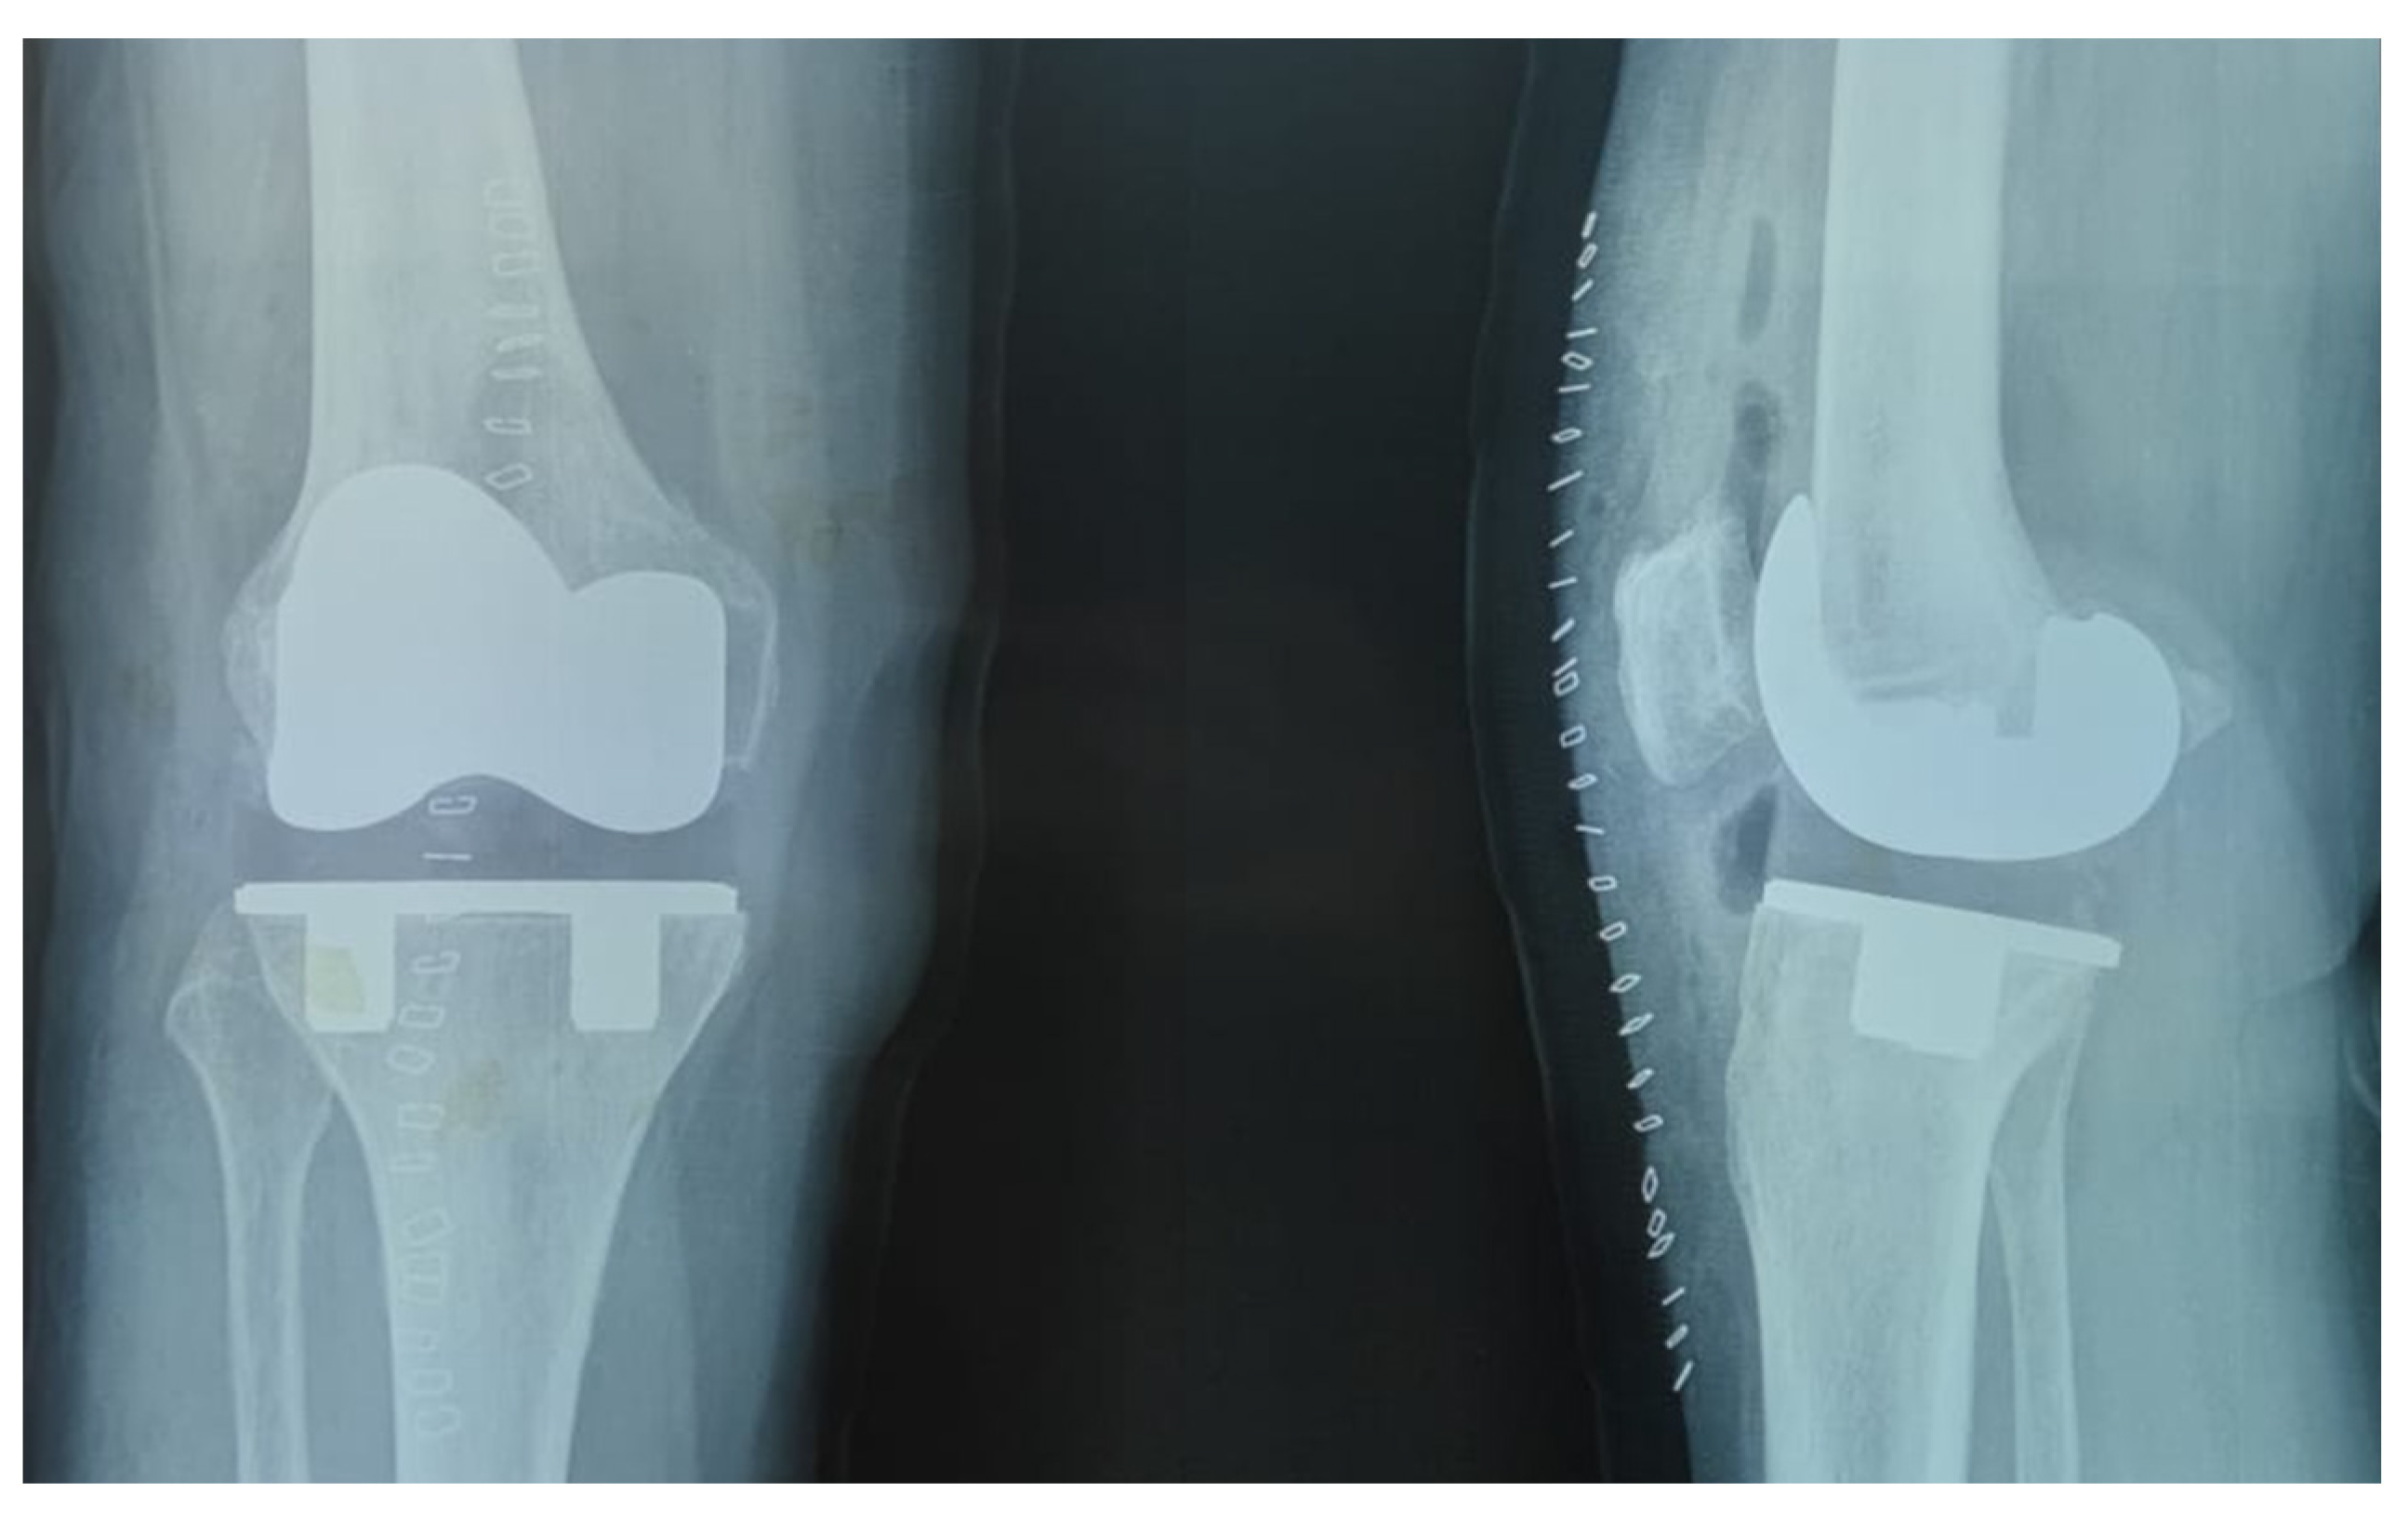

Figure 3.

Radiographic image of a TKA using a three-peg modular TMT tibial component.

Figure 4.

Radiographic image of a TKA using a two-peg monoblock TMT tibial component.